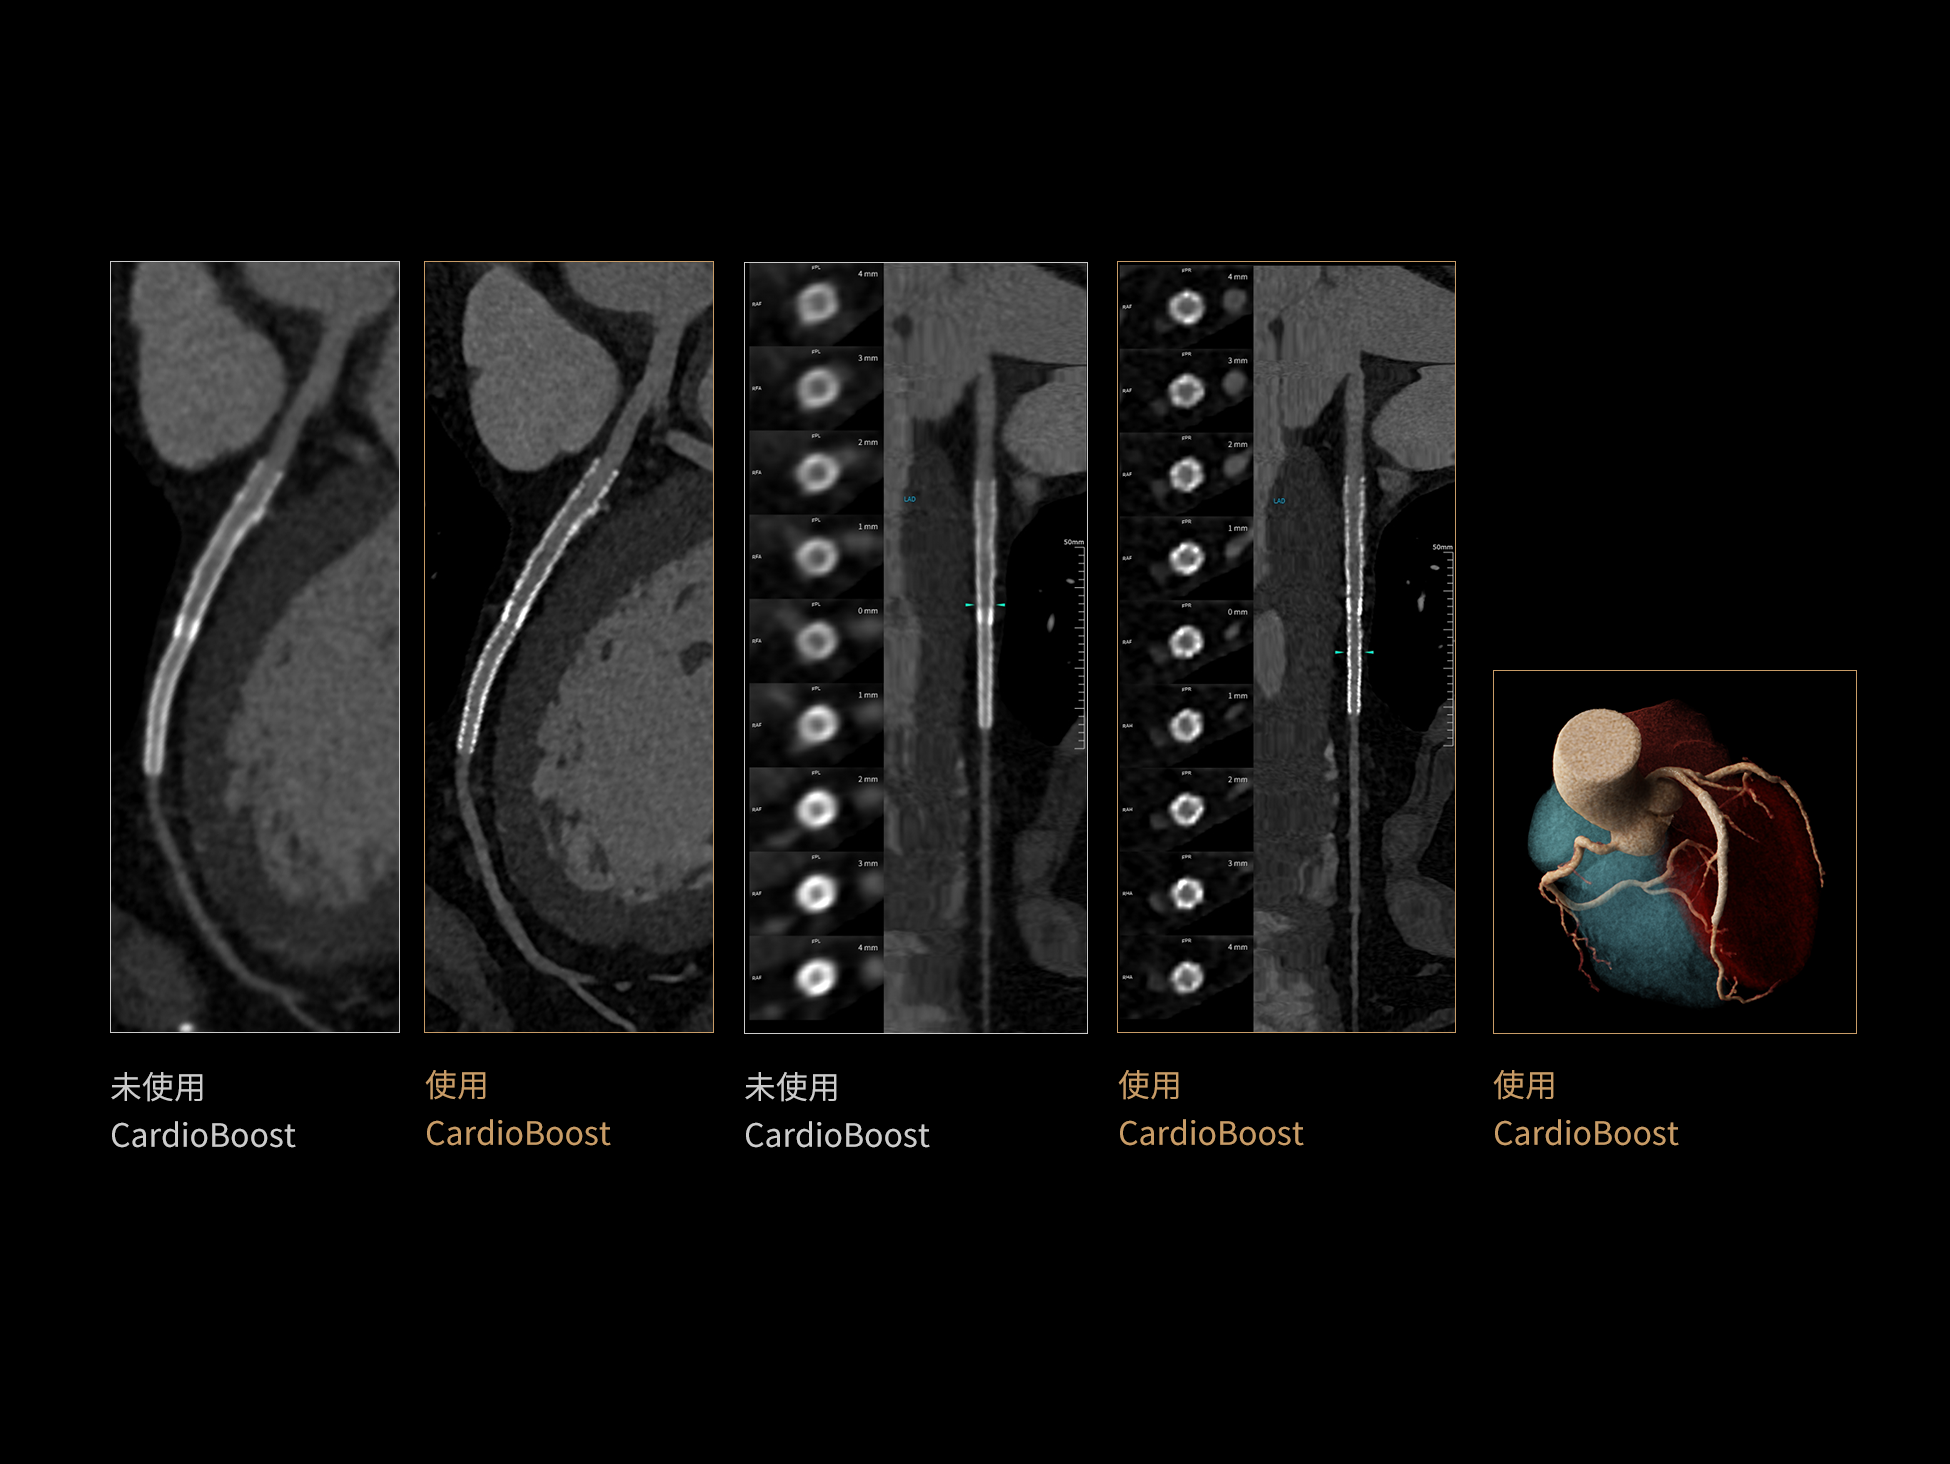

相同低对比度分辨率下

辐射剂量减少

相同辐射剂量条件下

图像噪声减少